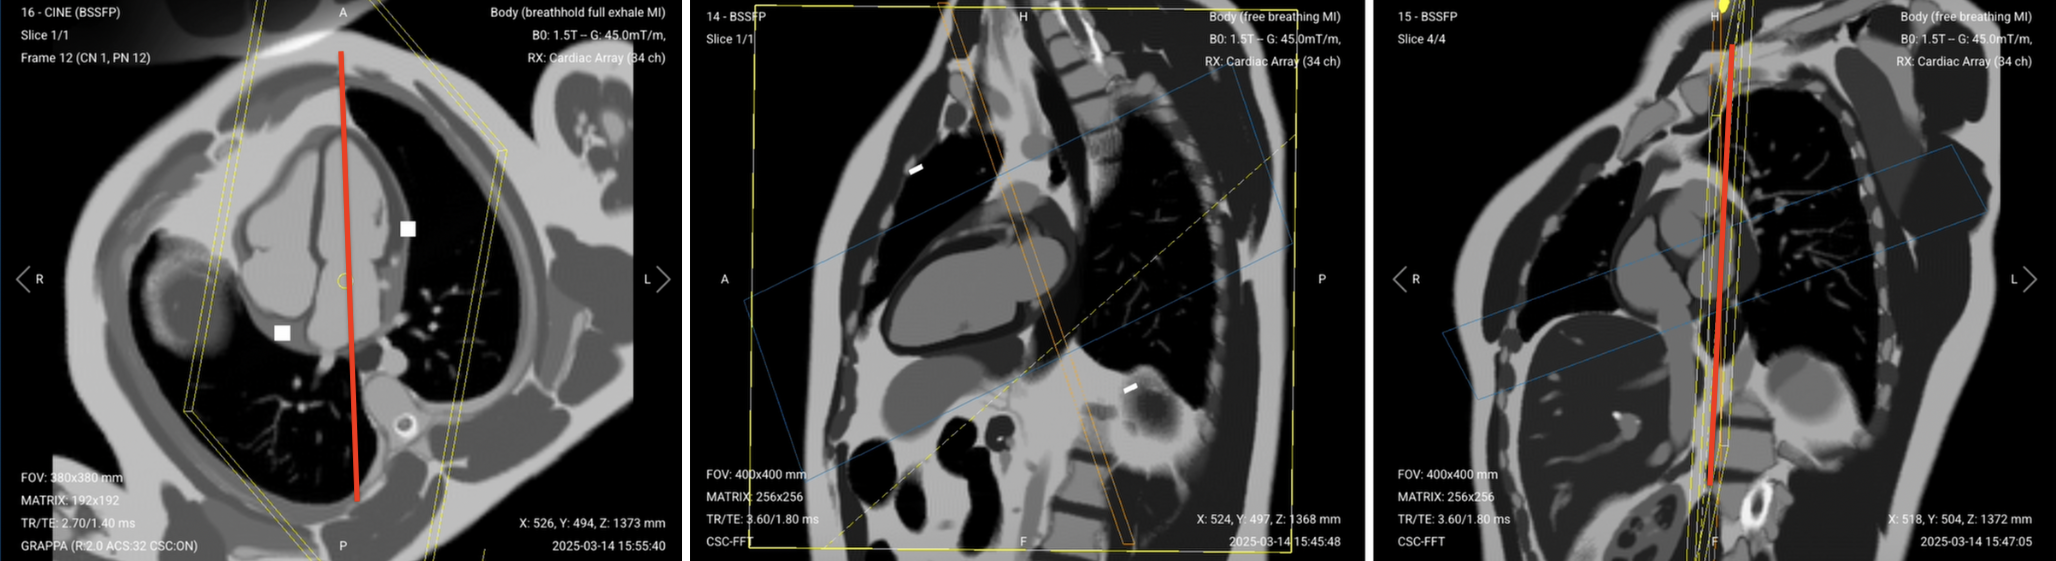

1. Short-Axis (SAX) Perfusion GRE

The perfusion sequence tracks contrast as it flows through the heart muscle. We capture three slices (basal, mid, and apical) to see the entire left ventricle.

Start the perfusion sequence and acquire 8–10 baseline images. Then inject contrast and capture another 45–50 phases as it washes through.

Watch for the contrast arriving in the right ventricle first, then left ventricle, then myocardium. Normal tissue enhances uniformly. Dark areas indicate perfusion defects.

For patients with poor cardiac function, increase phases to 80–100. The slow-moving heart needs more time points to capture the full contrast passage.

✅ Correct Planning:

Correct Planning of Short-Axis (SAX) Perfusion GRE

Planning Instructions:

• Plan the stack using the 2-chamber cine and 4-chamber cine views.

• Use the left ventricle and mitral valve as your anatomical references.

• Align the slices as follows:

• 2-chamber cine: Position slices perpendicular to the long axis of the left ventricle. Space them evenly from base to apex.

• 4-chamber cine: Ensure slices are perpendicular to the interventricular septum and cover the full left ventricle.

• Use appropriate geometry parameters:

• Slice number: 3 slices (basal, mid, apical) to cover key myocardial regions.

• Slice thickness: 8–10 mm for adequate coverage with good SNR.

• Slice gap: 8–10 mm between slices to avoid overlap while covering the full ventricle.

• Set the fold-over direction (phase encoding) to right–left (RL) to minimize wrap artifacts from the chest wall.